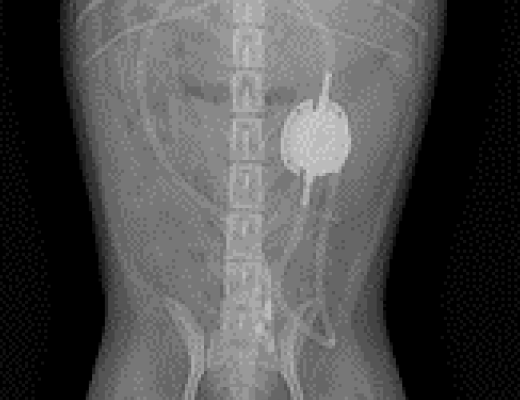

· 방사선 검사

방사선 검사는 방사선 상에서 확인될 수 있는 결석의 개괄적인 위치 파악에 있어 중요하게 작용합니다. 방사선 상 명확하게 보이는 결석 또는 이차적인 신장의 비대 소견이 확인되게 되면, 실제 신장 및 요관에서 발생한 형태 변화를 확인하기 위해 초음파 검사를 진행하게 됩니다.

1-1 1-2

요관 폐색으로 인해 SUB 수술적 치료 진행